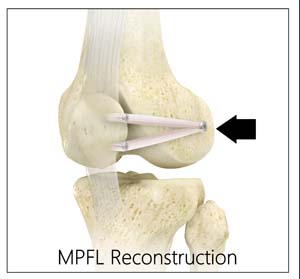

MPFL The Little Ligament That Could ProActive Physical Therapy online, Medial Patello Femoral Ligament MPFL Reconstruction online, Patellofemoral Ligament Reconstruction Knee Surgeon South online, Arthroscopic reconstruction of the medial patellofemoral ligament online, Medial Patellofemoral Ligament Tears Minneapolis MN Sports online, Medial Patellofemoral Ligament Reconstruction Techniques online, Patellofemoral Instability in the Skeletally Immature Patient A online, Medial Patellofemoral Ligament Surgery In Tamilnadu online, Physical Therapy for Medial Patellofemoral Ligament Injury online, PDF Management of medial patellofemoral ligament injury A case online, Medial Patellofemoral Ligament Injury MPFL Specialist Sugar online, Arthroscopy Journal on X online, The Medial Patellofemoral Ligament of the Knee by Nabil Ebraheim online, Figure 4 from The medial patellofemoral ligament Review of the online, Medial patellofemoral ligament reconstruction technique online, Graphic illustration of double bundle medial patellofemoral online, MPFL reconstruction animation online, What is the difference between MCL and MPFL ligaments and does online, Dynamic Anatomical Reconstruction of Medial Patellofemoral online, MPFL Injury Medial Patellofemoral Ligament MPFL Tear online, Your Patellofemoral Ligaments and Cartilage Spring Loaded Technology online, MPFL Reconstruction Hertfordshire Patellar Instability online, Medial Patellofemoral Ligament Reconstruction Complete Orthopedics online, Medium to long term outcomes of medial patellofemoral ligament online, Figure Diagram of the patellofemoral ligaments. Contributed by online, Medial Patellofemoral Ligament Tear Moreno Valley CA MPFL online, Medial Patellofemoral Ligament Of The Knee Anatomy Everything You Need To Know Dr. Nabil Ebraheim online, The Medial Patellofemoral Ligament MPFL The Basics BSM Foundation online, Medial Patellofemoral Ligament MPFL Reconstruction Knee online, Medial Patellofemoral Ligament MPFL Gorav Datta online, Medial Patellofemoral Ligament Reconstruction Sydney Knee online, Medial Patellofemoral Ligament Injury Recovery Capital Area PT online, Medial Patellofemoral Ligament MPFL Reconstruction HSS online, Medial Patellofemoral Ligament Injury MPFL Tear MPFL online, Medial Patellofemoral Ligament MPFL Physiopedia online, Product Info: Medial patellofemoral ligament online.